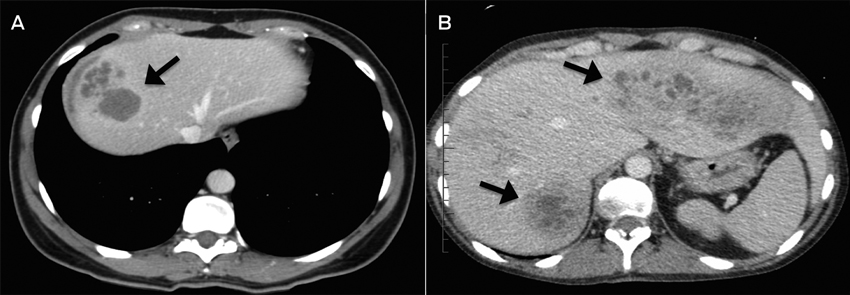

Radiological findings are often non-specific for fascioliasis. Ultrasonography and CT images often show poorly circumscribed lesions during the liver parenchymal phase.3

A: Case 3; CT image showing multiloculated hepatic lesions (arrow), central cystic changes and necrosis. B: Case 2; CT image showing irregular lesions (arrows) through both left and right hepatic lobes.